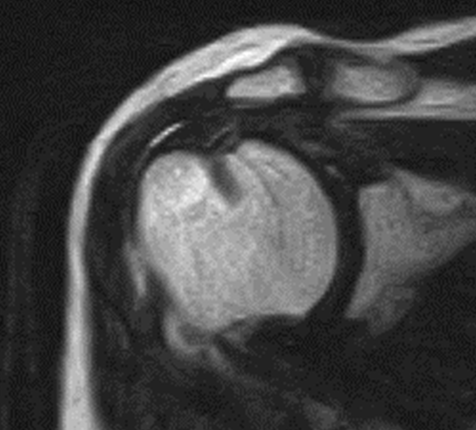

腱板断裂1

腱板断裂2

腱板断裂3